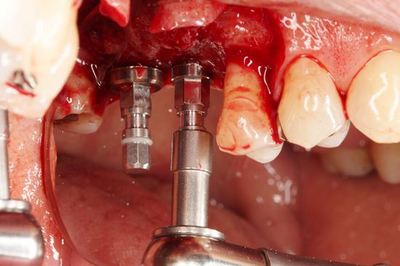

スリーブの長さがありますので狭い口腔内でドリルを挿入するのは

熟練が必要です。

![]()